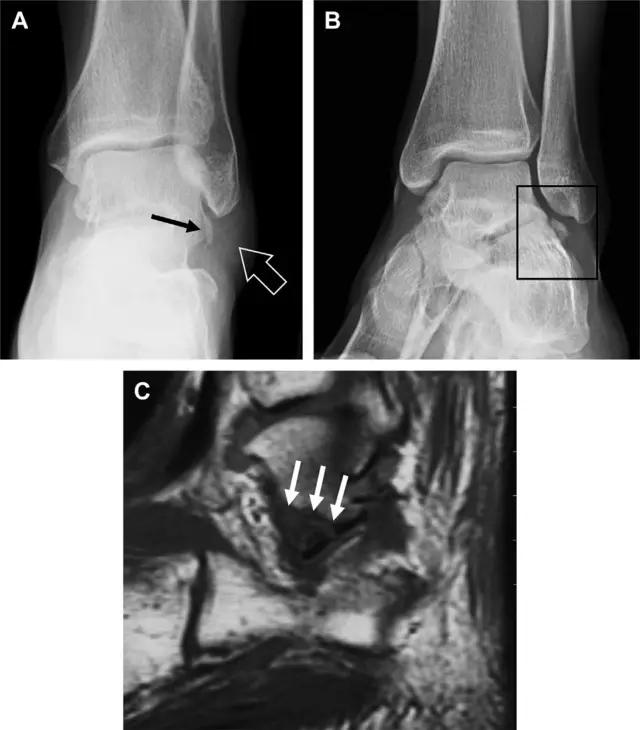

20 跟骨前突骨折

呈 Y 形的分歧韧带附着于跟骨前突上,是维持踝关节跖屈和背屈稳定性的重要结构。跟骨前突骨折常发生于足跖屈内旋、分歧韧带被牵拉时,或者足背屈外旋、骰骨和距骨挤压前突时。而这些骨折在初次 X 线检查时常常被漏诊掉。踝部侧位片诊断这些骨折最佳,准确诊断的关键点在于,必须仔细查看是否存在骨皮质中断(图 6)。如果侧位片可疑,建议加做斜位片协助诊断。

图 6 跟骨前突骨折。A 侧位片示跟骨前突骨折(箭头),与舟骨的重叠使骨折显示模糊;B 另一位患者的侧位片示内翻损伤所致的骨折(箭头),这种损伤机制引起小块的骨折

21趾短伸肌跟骨撕脱性骨折

另一种重要的跟骨撕脱性骨折,于足内翻时发生在趾短伸肌的起点处。观察来自跟骨背外侧的、不同大小的骨折块,前后位 X 片最适合不过了(图 7)。

图 7 溜冰受伤的患者,趾短伸肌跟骨撕脱性骨折。正位片示 2 个骨折块(箭头)来源于跟骨前外侧、趾短伸肌的起点处。踝关节外侧远端是否存在软组织水肿是一个重点观察点

22 跗跖关节复合体(Lisfranc 关节复合体)损伤

与跗跖关节韧带相关的骨折常由旋前或旋后的跖屈损伤引起。尽管跗跖关节骨折脱位仅占所有骨折的 0.2%,但是约 20% 的这些骨折在初次检查时被漏诊。初次 X 片可能示正常,但是负重位 X 线片常常提示脱位或半脱位。

典型表现:第二跖骨底和内侧楔骨之间的骨折碎片,跖骨间间隙增宽(图 8)。脱位亦可发生在舟骨-内侧楔骨关节,导致另一种变异的跗跖关节损伤(图 9A)。此外,骰骨的小块皮质撕脱在足部斜位片上可清晰显示(图 9B)。

图 8 从马上摔落的患者,跗跖关节骨折。A 正位片示内侧楔骨旁边的小骨折碎片(箭头),第二跖骨底向外半脱位;B 负重位侧位片示第二跖骨相对中间楔骨向背侧轻微移位(长方形);C STIR 序列 MRI 图像示跗跖关节韧带断裂(箭头),第一至第三跖骨、内侧楔骨及中间楔骨均骨髓水肿

图 9 变异的跗跖关节骨折。A 另一种类型的跗跖关节损伤,中间楔骨向内侧半脱位(弧形箭头),从而使第一、第二跖骨间间隙变宽,需注意,骨折在靠近内侧楔骨处(箭头);B 外侧跗跖关节损伤伴随从骰骨跖骨韧带的骰骨撕脱(箭头),需注意,第五跖骨底近端处存在软组织水肿(空箭头)